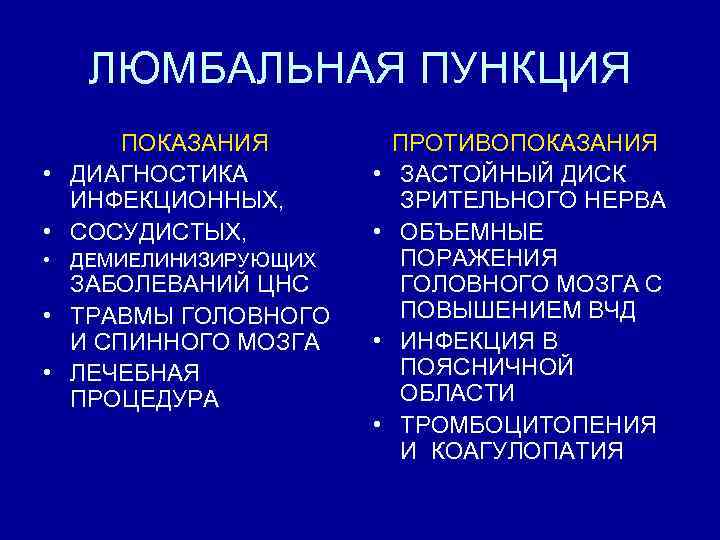

ЛЮМБАЛЬНАЯ ПУНКЦИЯ ПОКАЗАНИЯ • ДИАГНОСТИКА ИНФЕКЦИОННЫХ, • СОСУДИСТЫХ, • • • ДЕМИЕЛИНИЗИРУЮЩИХ ЗАБОЛЕВАНИЙ ЦНС • ТРАВМЫ ГОЛОВНОГО И СПИННОГО МОЗГА • ЛЕЧЕБНАЯ ПРОЦЕДУРА • • ПРОТИВОПОКАЗАНИЯ ЗАСТОЙНЫЙ ДИСК ЗРИТЕЛЬНОГО НЕРВА ОБЪЕМНЫЕ ПОРАЖЕНИЯ ГОЛОВНОГО МОЗГА С ПОВЫШЕНИЕМ ВЧД ИНФЕКЦИЯ В ПОЯСНИЧНОЙ ОБЛАСТИ ТРОМБОЦИТОПЕНИЯ И КОАГУЛОПАТИЯ

ЛЮМБАЛЬНАЯ ПУНКЦИЯ ПОКАЗАНИЯ • ДИАГНОСТИКА ИНФЕКЦИОННЫХ, • СОСУДИСТЫХ, • • • ДЕМИЕЛИНИЗИРУЮЩИХ ЗАБОЛЕВАНИЙ ЦНС • ТРАВМЫ ГОЛОВНОГО И СПИННОГО МОЗГА • ЛЕЧЕБНАЯ ПРОЦЕДУРА • • ПРОТИВОПОКАЗАНИЯ ЗАСТОЙНЫЙ ДИСК ЗРИТЕЛЬНОГО НЕРВА ОБЪЕМНЫЕ ПОРАЖЕНИЯ ГОЛОВНОГО МОЗГА С ПОВЫШЕНИЕМ ВЧД ИНФЕКЦИЯ В ПОЯСНИЧНОЙ ОБЛАСТИ ТРОМБОЦИТОПЕНИЯ И КОАГУЛОПАТИЯ